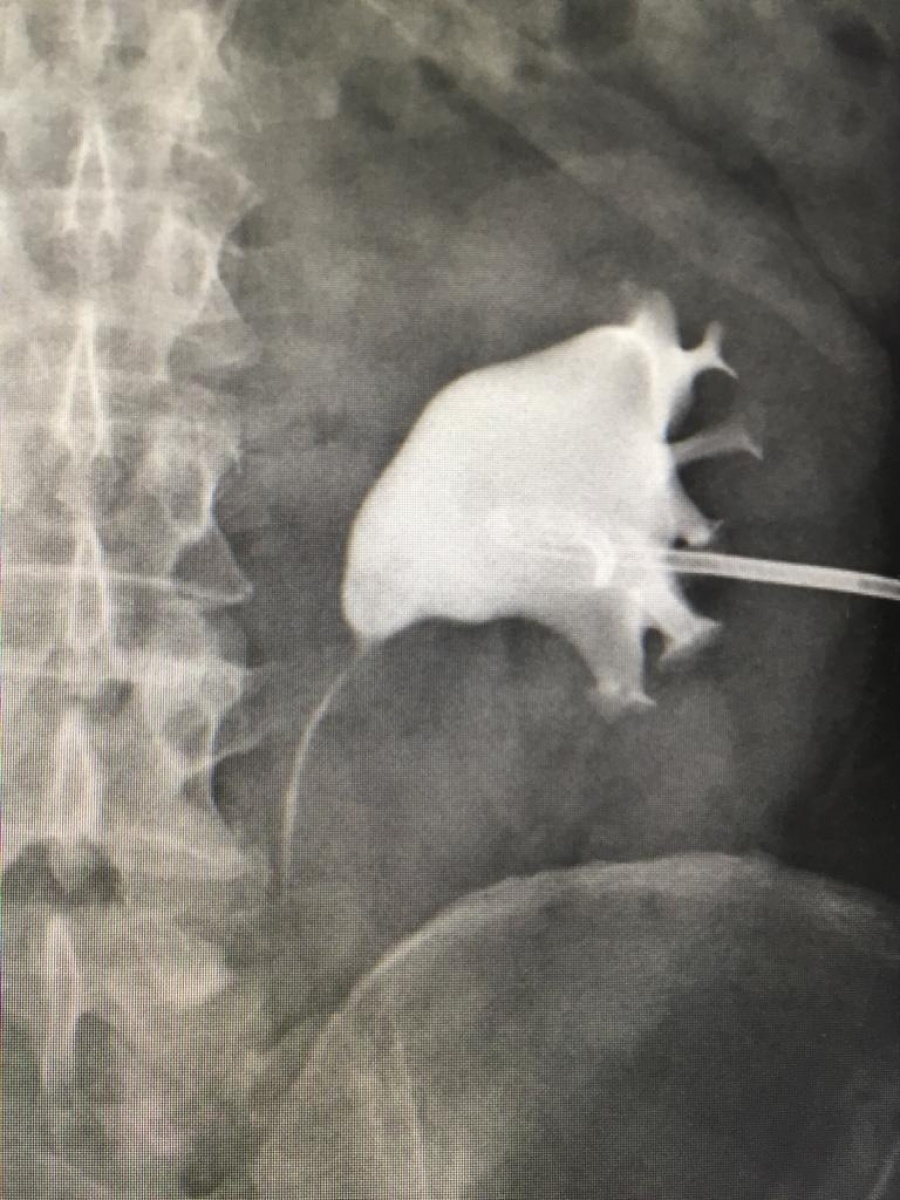

W ostatnich dniach w Samodzielnym Publicznym Zespole Opieki Zdrowotnej w Kędzierzynie-Koźlu zespół urologów przeprowadził nowatorski zabieg leczenia złożonej kamicy moczowej metodą ECIRS. Metoda ta polegającej na jednoczasowym usunięciu złogu nerkowego zajmującego całą nerkę (tzw. kamica odlewowa). Zabieg taki przeprowadzono po raz pierwszy w woj. opolskim.

Jest to jeden z najnowocześniejszych na świecie sposobów leczenia złożonych przypadków kamicy moczowej. Jak przestawili to lekarze urolodzy jest to cyt.: "Modyfikacja przezskórnej nefrolitotrypsji, która obecnie jest złotym standardem leczenia dużych złógów zlokalizowanych w nerkach."

Leczenie operacyjne polega tutaj na jednoczasowym, endoskopowym (małoinwazyjnym) dostępie do układu kielichowo-miedniczkowego nerki i precyzyjnym usunięciu złogu. Metoda ta jest przyszłością leczenia kamicy moczowej. Z uwagi na małą inwazyjność i precyzję ogranicza ona znacznie pole operacyjne i pomaga zdecydowanie szybciej wrócić pacjentowi do pełnej sprawności. Zabieg ten jest obecnie wykonywany jedynie w zaawansowanych jednostkach medycznych i wymaga specjalistycznego sprzętu oraz wykwalifikowanego, wielozadaniowego zespołu.

Jak powiedział Kierownik Oddziału Urologii i Onkologii Urologicznej lek. med. Michał Pułtorak – Operowany przez nas Pacjent miał złożony typ kamicy moczowodowej i kamicę kielicha dolnego nerki lewej. Stąd decyzja o wykonaniu tego typu zabiegu. Zabieg przeprowadziliśmy korzystając ze wszystkich dostępnych nowoczesnych urządzeń m.in lasera, maloinwazyjnego zestawu do pcnl i ureterorenoskopu półsztywnego. Dzięki współpracy specjalistów udało się usunąć złogi całkowicie.